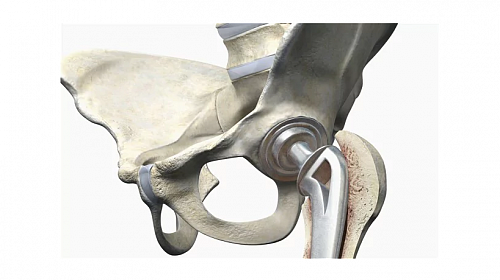

Предприятие ОРТОпедияНИКифорова было основано в 1998 г. кандидатом мед. наук врачом ортопедом-травматологом высшей категории Никифоровым И.А. Благодаря высокому профессионализму и результатам работы, ОРТОНИК завоевал заслуженную известность и репутацию среди коллег и населения г. Днепропетровска области и стран СНГ (Россия, Молдавия, Армения и др.).

Принцип предприятия – НЕТ НИЧЕГО НЕВОЗМОЖНОГО, основан на знаниях, опыте и активном внедрении современных технологий в ортопедии и травматологии.

- Достижения протезирования Декабрь 10, 2017